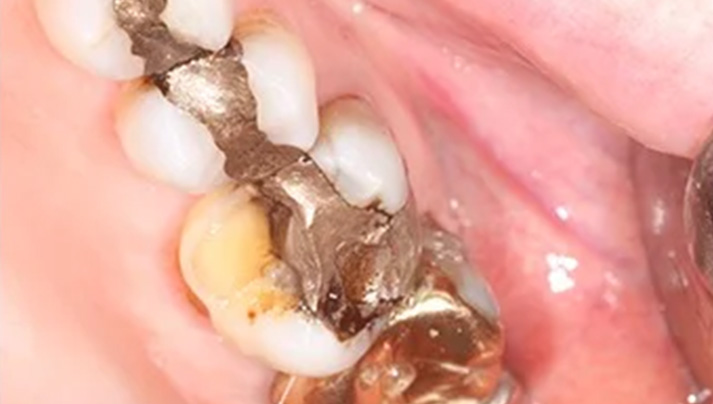

Before and Afters – White Fillings